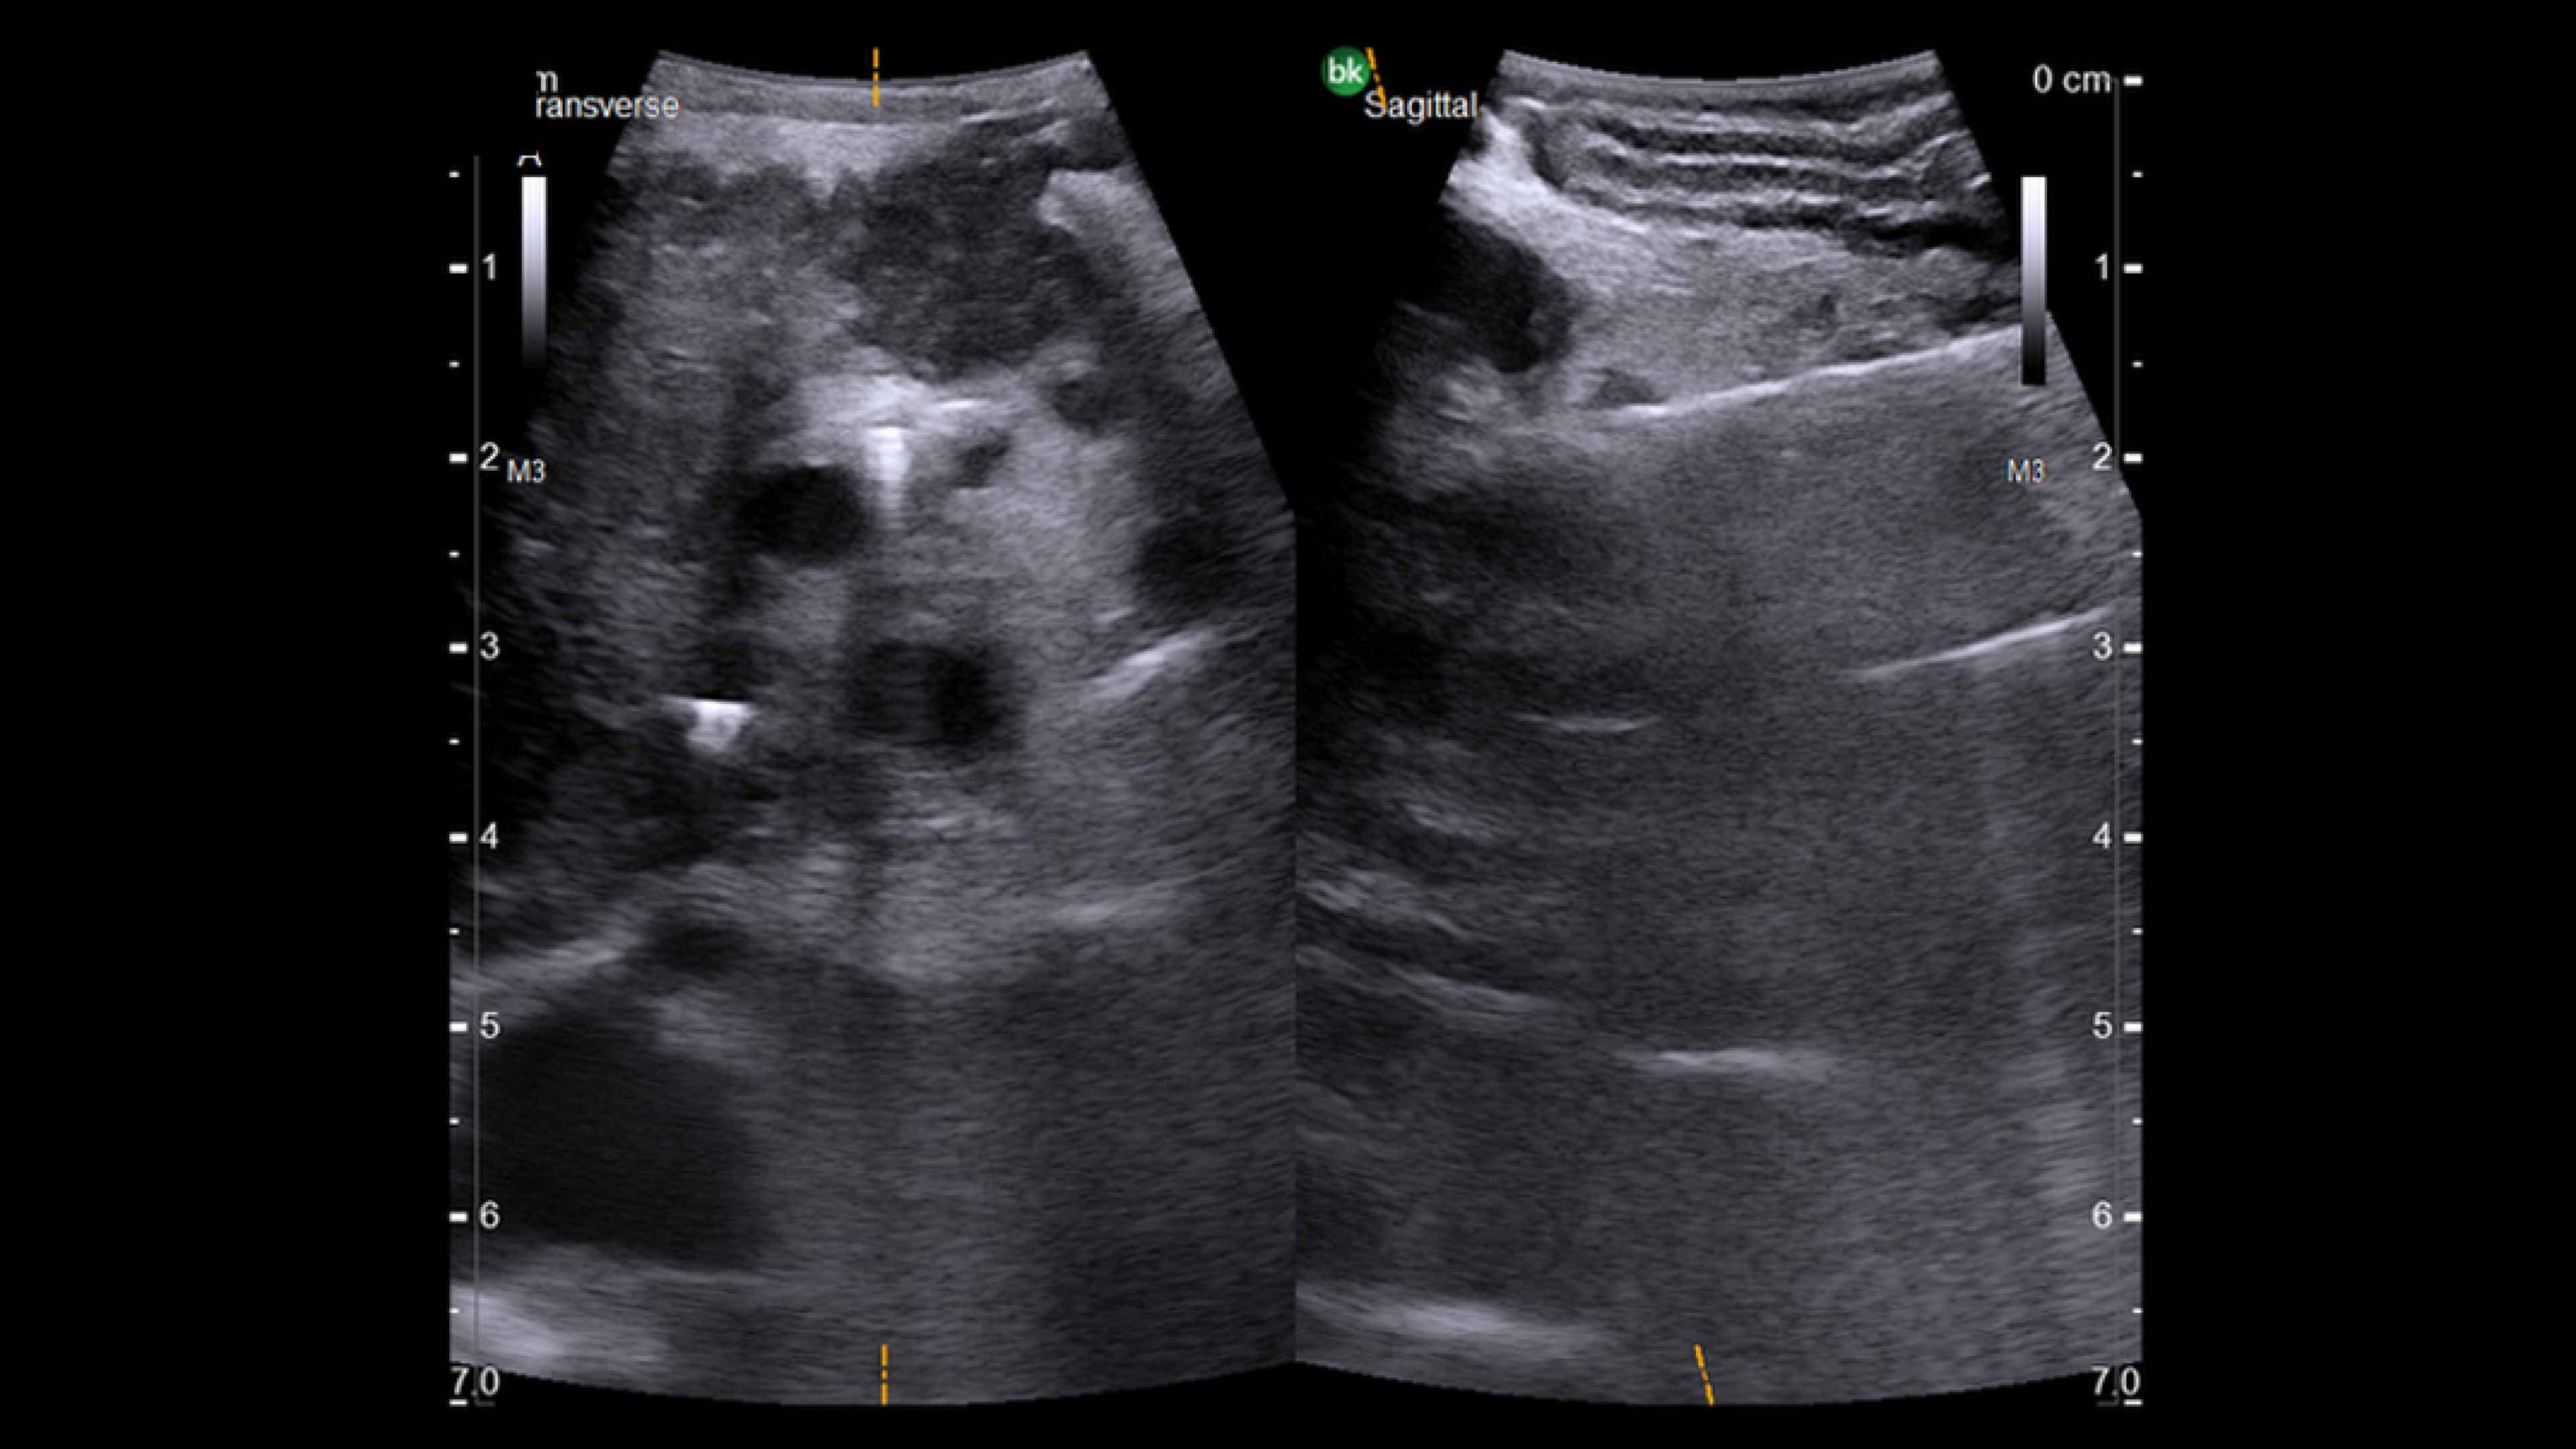

Active imaging supports liver and pancreas tumor resection procedures by helping you visualize complex anatomical variations and relationships to vascular structures, identify tumor location, define adequate margins of resection, and assess surgical planning.

Active imaging with intraoperative ultrasound supports critical decision-making in open or minimally invasive tumor resections.

• Visualize complex anatomical variations.

• Identify tumor location, proximity, and invasion of vasculature.

• Define adequate margins of resection.

• Understand relationship to vascular structures.

• Assess surgical planning and check for vessel patency at the end of the procedure.

Use of ultrasound during complex redo open liver resection.